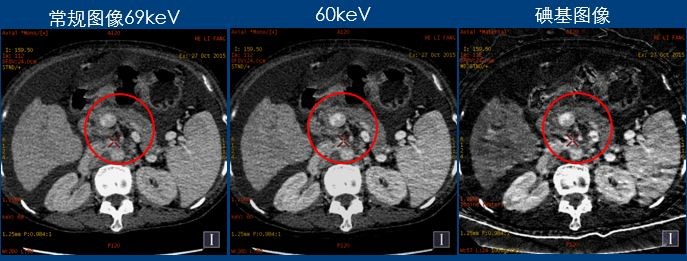

门静脉显示在60Kev对比度更高,碘基图对含碘的结构显示非常敏感

CT诊断:考虑原发性肝癌(弥漫结节型),门静脉主干癌栓形成。 小结:肝脏具有肝动脉和门静脉双重血供特点,肝硬化时由于门脉压力升高,导致门脉血供减少,为保证肝脏的营养肝动脉供血相对增加即肝动脉缓冲效应(hepatic arterial buffer response,HABR),以致肝脏的双重血供比例失调。能谱CT可以实现物质分离功能,能够直接测量肝脏增强扫描各期肝实质的碘含量,并可计算出肝动脉碘分数(arterial iodine fraction,AIF& #41; 与门静脉碘含量(portal venous iodine concentration ,PVIC & #41; .本例通过肝脏病变血供情况的定量分析 ,提供更多诊断信息。 致谢:番禺中心医院